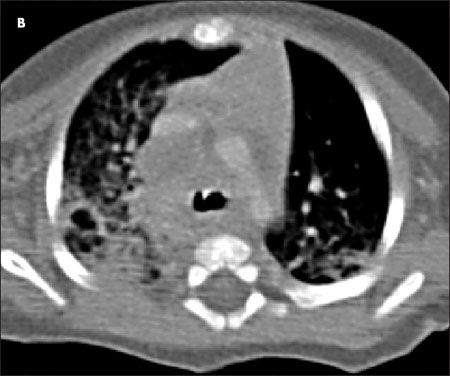

A CT scan of the thorax was ordered to help determine whether a recurrent pulmonary embolism may have contributed to a 54-year-old man's arrhythmia. He also had a history of giant bullous emphysema, or “vanishing lung syndrome,” a rare condition caused by paraseptal emphysematous bullae that coalesce and eventually compress the lung parenchyma. The bullae can be mistaken for a pneumothorax on a standard chest film.

Image courtesy of Mark Masciocchi, MD, Shashank Jain, MD, and Anthony Donato, MD.